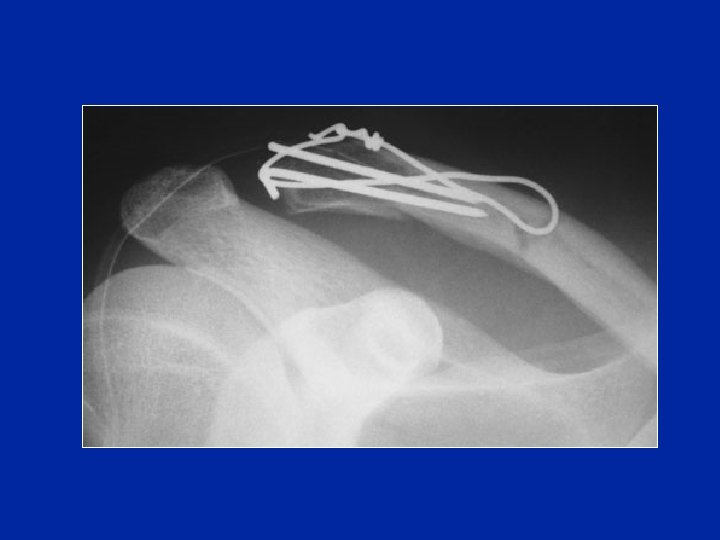

Traitement chirurgical Fractures distales : hauban (broches et fil en 8)

Traitement chirurgical But : maintenir en place la clavicule pendant la cicatrisation des ligaments Broche Acr-clav temporaire Laçage entre clavicule et coracoïde

Stabilisation provisoire pendant la cicatrisation Laçage acr-clav + sutures Vis entre clavicule et coracoÏde Broche